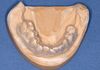

)

BILD 1: Kongresslayout BILD 2: Dr. Horst-Uwe Klapper BILD 3: Prof. Dr. Nadine Schlüter BILD 4: Priv. Doz. Dr. Christoph Runte BILD 5: Patient mit entferntem Gaumendach BILD 6: Obturator (Defektprothese) BILD 7: Strahlenschutzschiene BILD 8: Defektprothese (Obturator) mundseitig BILD 9: Defektprothese (Obturator) nasenseitig